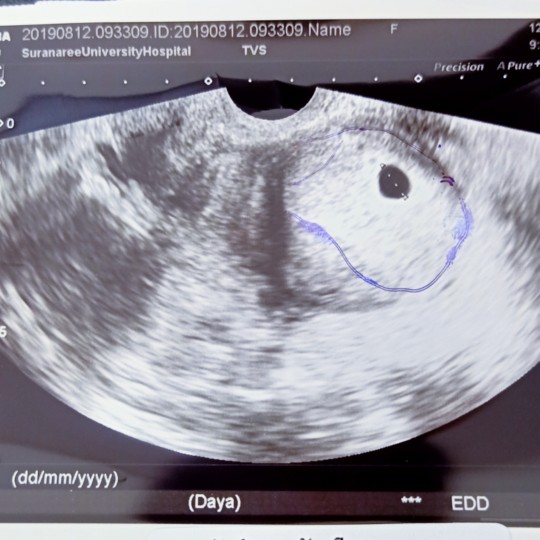

ไปฝากครรภ์ตอน6w+6 อัลตร้าซาวด์เจอแต่ถุงค่ะ กังวลมากๆ กลัวท้องลมหรือแท้ง ?? #อัพเดตจ้า ตอนนี้น้องคลอดแล้วนะค่ะ. ? น้องข้าวแป้งอภิสรา 12กุมภาพันธ์63จ้า

รออีกนิดค่ะ ถุงกลมสวยน่าจะไม่ใช่ท้องลมนะคะ